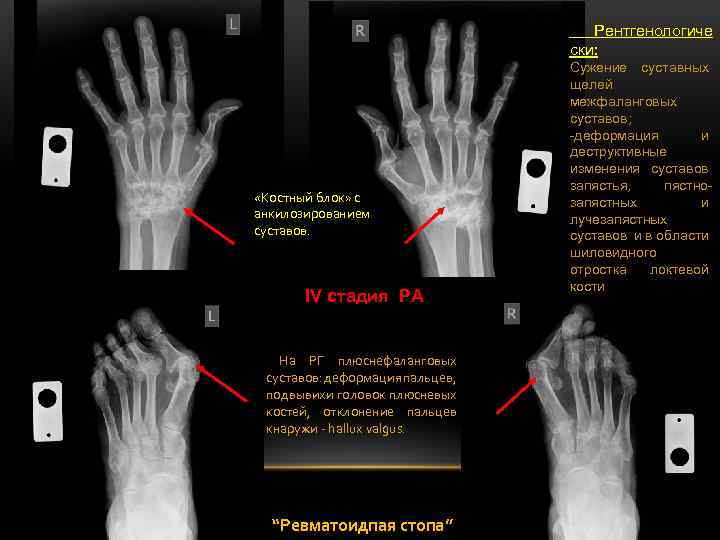

III- IV стадия РА На РГ суставов запястья: деструкция мелких костей с образованием единого «костного блока» . В проксимальных межфаланговых суставах эрозивные изменения. о/с остеопороз+ сужение суставных щелей+ эрозиивные изменения суставных поверхностей + анкилозы суставов На РГ вальгусная деформациия большого пальца слева, подвывихи пальцев с их смещением и отклонением в латеральную сторону; зрозивнодеструктивные измнения в головках

Рентгенологиче ски: «Костный блок» с анкилозированием суставов. IV стадия РА На РГ плюснефаланговых суставов: деформация пальцев, подвывихи головок плюсневых костей, отклонение пальцев кнаружи - hallux valgus. “Ревматоидпая стопа” Сужение суставных щелей межфаланговых суставов; -деформация и деструктивные изменения суставов запястья, пястнозапястных и лучезапястных суставов и в области шиловидного отростка локтевой кости